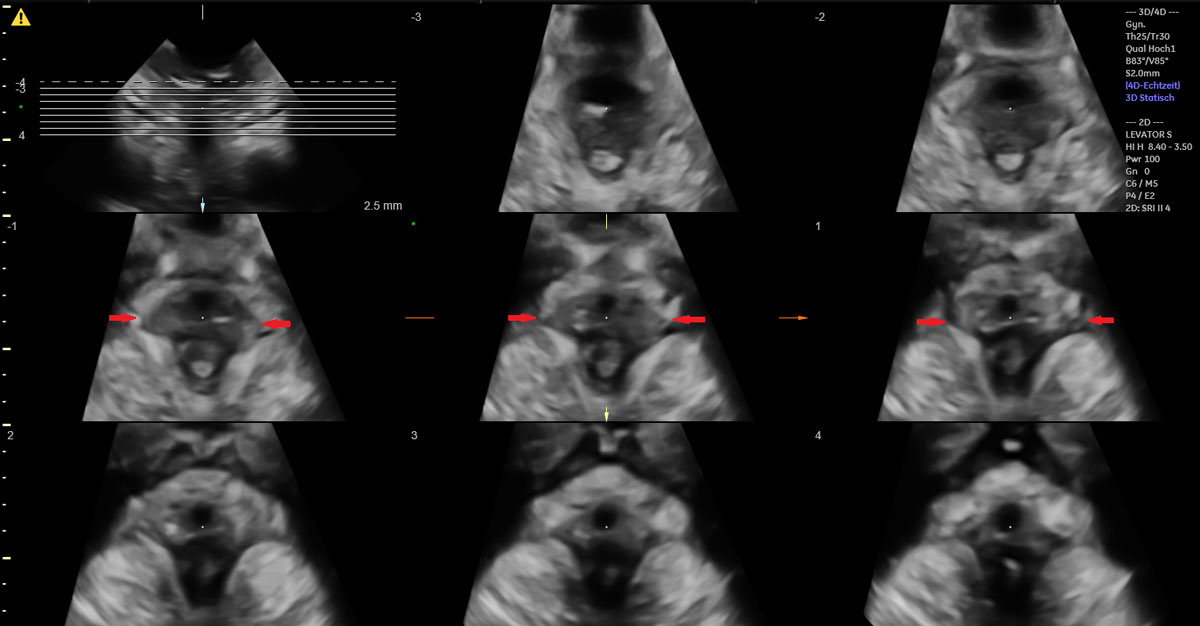

Between March 2017 and April 2019, we asked nulliparous women ≥18 of age with singletons in vertex presentation at ≥36+0 gestational weeks (gw) at the University Hospital of Zurich who planned to have a vaginal birth in our institution to participate in a prospective cohort study for the evaluation of levator ani muscle trauma after vaginal birth. The study was approved by the local ethics board and was performed according to the Declaration of Helsinki. Within this prospective observational cohort study, all women who gave birth with the help of vacuum extraction were included in the final analysis for the presented study. Clinical data were extracted from the institutional obstetric database (Perinat version 6.1.9.45) with the help of different observation and monitoring tools, as described by our group previously [33]. In our institution, we document in detail every step of vacuum extraction and its accompanying procedures in a special computerised report, including photo documentation of cup placement on the fetal head [33, 34]. Therefore, multiple parameters of the vacuum extraction procedure, as well as fetal and maternal characteristics, could be evaluated in our study. Levator ani muscle injury was assessed by 3D translabial ultrasound 6–10 weeks after birth, conducted by two well-trained pelvic floor sonographers. Prior to the examination, women were asked to empty their bladder and were placed in the lithotomy position. A covered 4–7 MHz 3D abdominal probe (Voluson S10, GE Healthcare, Zipf, Austria) was then placed between the labia. Acquisition and interpretation of 3D tomographic volumes was performed as described previously by Dietz et al. [20, 22]. We documented each discontinuity (a break in the normal texture of the pubococcygeal-puborectalis muscle, evident as an ultrasound hypo-/anechogenic lesion interrupting the hyperechogenic course of muscle fibres) involving the pubococcygeus-puborectalis muscle recognisable in the coronal C-plane slice (unilateral if the defect involves one side, bilateral if both sides are damaged). Levator ani muscle status was then classified into levator ani muscle trauma in the form of partial or complete avulsion or intact levator ani muscle, as described by Dietz et al. [20, 21, 35]. Levator ani muscle avulsion was diagnosed as a partial avulsion if an abnormal insertion of the levator ani muscle to the pubic bone was evident in at least one slice, and as a complete avulsion if an abnormal insertion was found in all three central slices at the level of the plane of minimal hiatal dimension and at 2.5 and 5 mm above this plane. A univariate analysis was performed to evaluate the association of levator ani muscle injury with different possible risk factors of interest, using a chi-square test for categorical variables and Student's t-test for continuous variables. In the case of several single parameters being statistically significant, a multivariate analysis was planned in as second step. Statistical significance was set at a level of <0.05. No power calculations were performed, as this was a secondary analysis of the above-mentioned main prospective study.

Of the 49 women with vacuum-assisted births in our cohort, 32 (65.3%) had an intact levator ani muscle, as shown in the illustration in fig. 2a and in the 3D ultrasound scan in fig. 2b. In contrast, 17 (34.7%) sustained levator ani muscle trauma, with 9 women (18.4%) having a partial levator ani muscle avulsion and 8 women (16.3%) having a complete levator ani muscle avulsion, as shown in the illustration in fig. 3a and in the 3D ultrasound scan in fig. 3b. No significant differences between the two groups were found, except for the state of their uterine contractions. Women without any levator ani muscle injury after vacuum extraction had more efficient uterine contractions compared to women with levator ani muscle trauma.

Figure 3a Illustration of a complete bilateral levator ani muscle avulsion.

Figure 3b 3D translabial ultrasound image of a complete bilateral levator ani muscle avulsion.